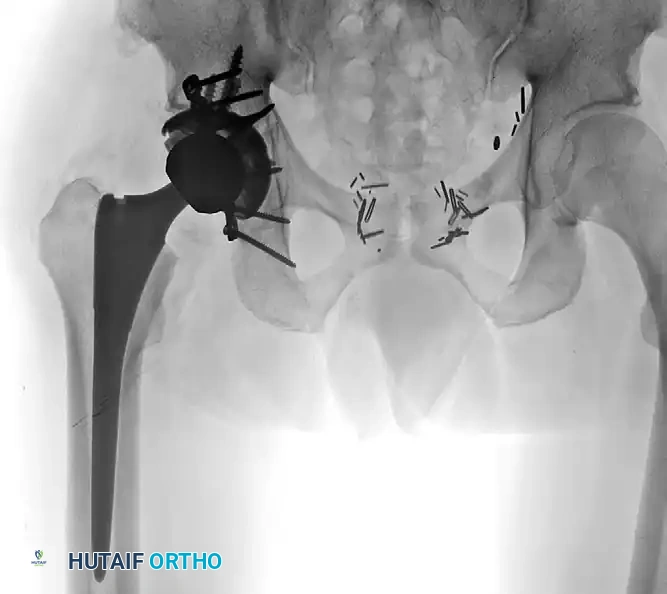

Postoperative AP radiograph illustrating the combined treatment: acute fracture fixation with posterior plating, integrated with a primary total hip arthroplasty utilizing a multi-hole cup and multiple supplementary screws for rigid construct stability.